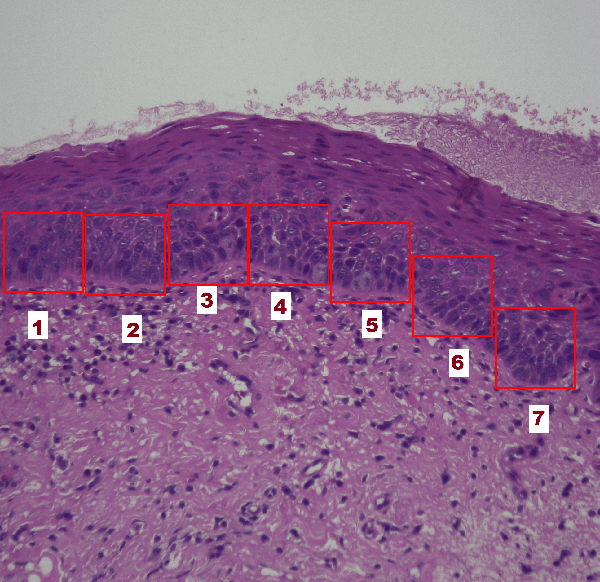

A Pathology-Based Machine Learning Method to Assist in Epithelial Dysplasia Diagnosis

Abstract:The Epithelial Dysplasia (ED) is a tissue alteration commonly present in lesions preceding oral cancer, being its presence one of the most important factors in the progression toward carcinoma. This study proposes a method to design a low computational cost classification system to support the detection of dysplastic epithelia, contributing to reduce the variability of pathologist assessments. We employ a multilayer artificial neural network (MLP-ANN) and defining the regions of the epithelium to be assessed based on the knowledge of the pathologist. The performance of the proposed solution was statistically evaluated. The implemented MLP-ANN presented an average accuracy of 87%, with a variability much inferior to that obtained from three trained evaluators. Moreover, the proposed solution led to results which are very close to those obtained using a convolutional neural network (CNN) implemented by transfer learning, with 100 times less computational complexity. In conclusion, our results show that a simple neural network structure can lead to a performance equivalent to that of much more complex structures, which are routinely used in the literature.